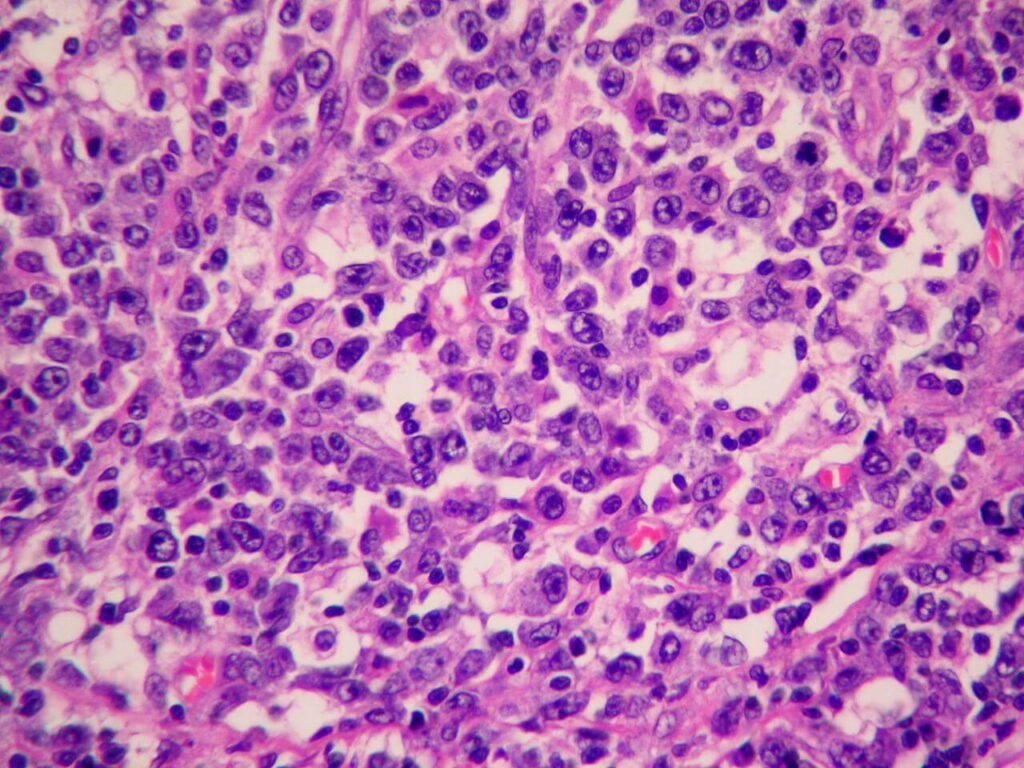

- Биопсия обнаруженного новообразования для проведения гистологического, иммуногистохимического анализа;